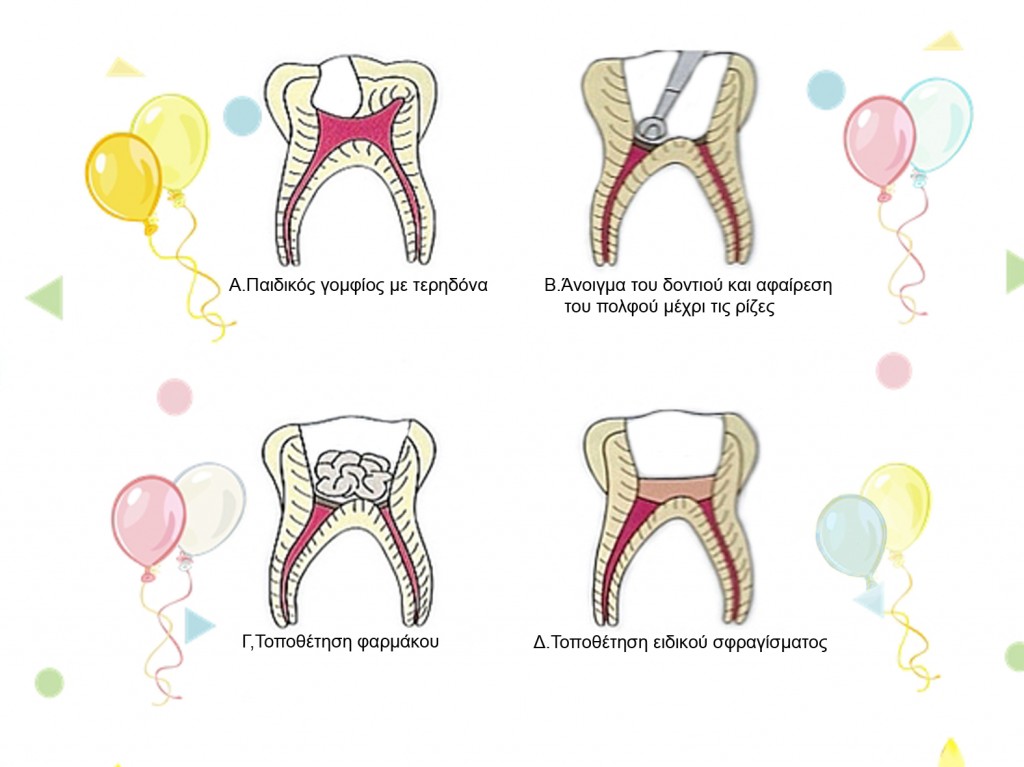

Όταν η τερηδόνα φτάσει πάρα πολύ κοντά στο νεύρο του παιδικού δοντιού, τότε η αντιμετώπιση με σφράγισμα δεν αρκεί διότι ο πολφός (το νεύρο του δοντιού) κινδυνεύει από φλεγμονή και υπάρχει κίνδυνος νέκρωσής του.

χρειάζεται να γίνει πολφοτομή, κατά την οποία αφαιρείται μέρος του πολφού, μπαίνει φάρμακο στην κοιλότητα που ήταν ο πολφός και ειδικό σφράγισμα. Αν το δόντι έχει καταστραφεί αρκετά, τότε επιβάλεται η τοποθέτηση στεφάνης για να το προστατέψει.

ΔΙΑΔΙΚΑΣΙΑ